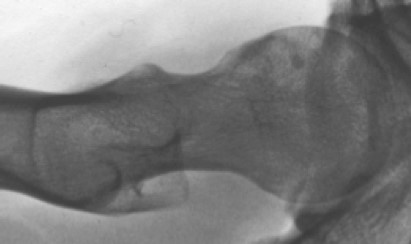

Bild: Lehrbuch Orthopädie. Was man wissen muss. Prof. Dr. Mazda Farshad. Springer 2021 © CC BY-NC 4.0

Wurde die Diagnose anhand des Röntgenbilds gestellt, ist die Magnetresonanztomographie (MRT bzw. engl. MRI für magnetic resonance imaging) mit Kontrastmittel die ergiebigste weiterführende Untersuchung. Dabei geht es darum, Risse der Gelenklippe (Labrum) zu erkennen, die Formstörung (Cam-Typ, Pincer-Typ, gemischter Typ) genau zu lokalisieren, die Verdrehung des Oberschenkelknochens (femorale Torsion) zu messen und Abnützungserscheinungen des Knorpels auszuschliessen. All diese Faktoren sind entscheidend für den weiteren Behandlungsplan. Die umfangreichen Untersuchungen erlauben, andere Diagnosen, die ähnliche Schmerzen provozieren können, auszuschliessen (Leistenbruch, Muskelzerrung, Muskelüberlastung, aber auch die Hüftdysplasie).